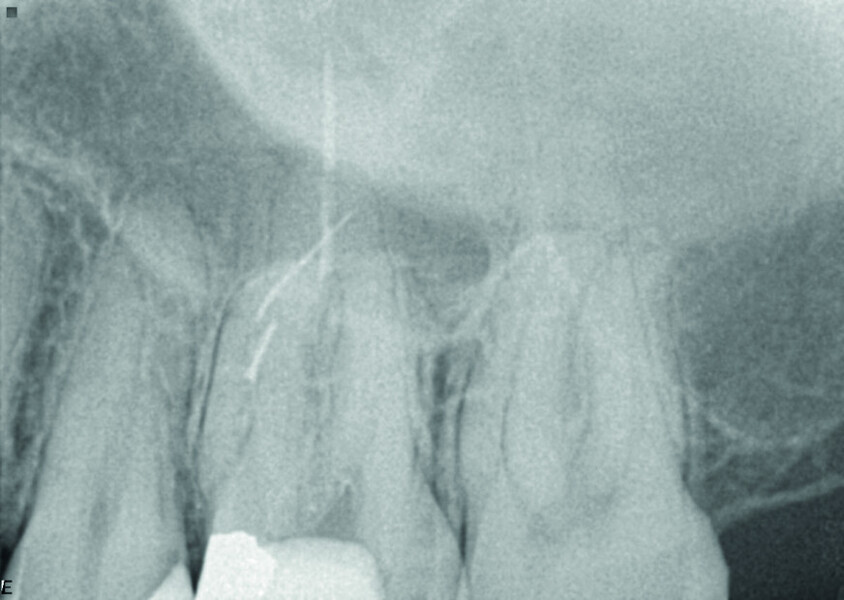

Maxillary sinus and root canal therapy complications